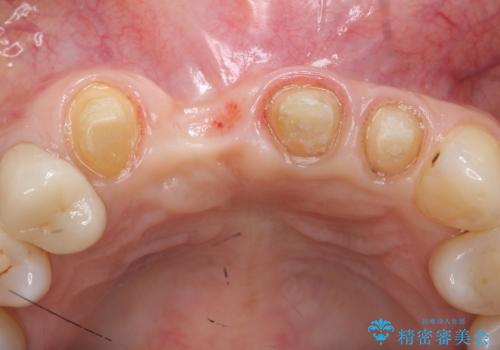

- 下顎前歯部の突き上げで上顎前歯の被せ物が土台ごと外れてしまった方の症例です。

右上1番目の歯は根元まで割れてしまっており、保存不可能だったため抜歯となりました。

抜歯後、骨と歯肉の回復を待ち、オールセラミッククラウンによるブリッジで補綴を行いました。